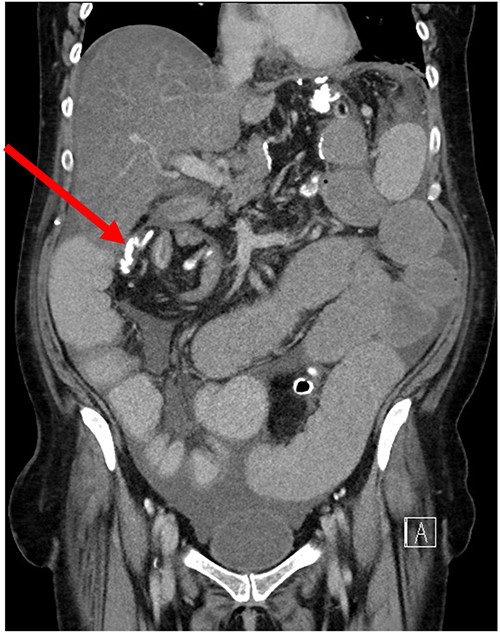

Her case was reviewed by a bariatric surgeon, who noted an internal hernia on CT causing the recurrent obstruction and subsequently planned for surgery (see Figs 2 and 3). On day 6, at the time of consenting for the procedure, she had a rapid neurological deterioration with fluctuating levels of consciousness (GCS10- E4V1M5), complete aphasia, bilaterally dilated pupils (9–10 mm), increased tone, hyper-reflexia and sustained clonus of 10+ beats in lower limbs. A broad list of differentials was considered due to her medical history. CT (Brain, head and neck angiogram and Venogram) scans reported no acute intracranial pathology, plasma ammonia level was 290 μmol/L (<50 μmol/L) (see Fig. 4), C-reactive protein (CRP) 44 mg/L (<10 mg/L) and ketosis with no acidosis.